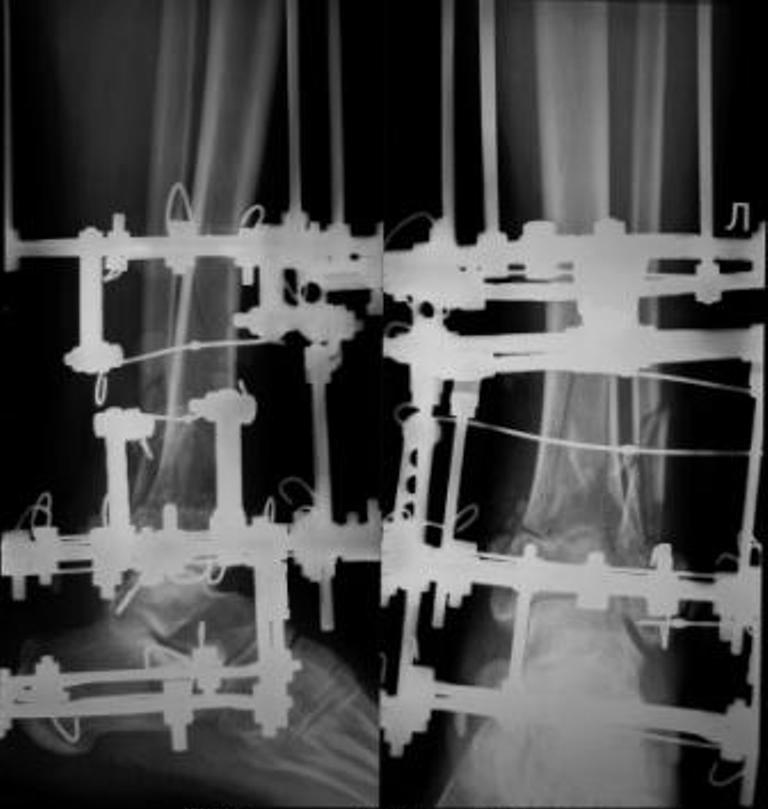

До лечения, в процессе, через 8 мес.

Перелом внутрисуставной. Конечно, не такой тяжелый ,как представленный, но эпифиз б/б кости тоже расколот пополам, это видно на боковом снимке плюс перелом наружной лодыжки.